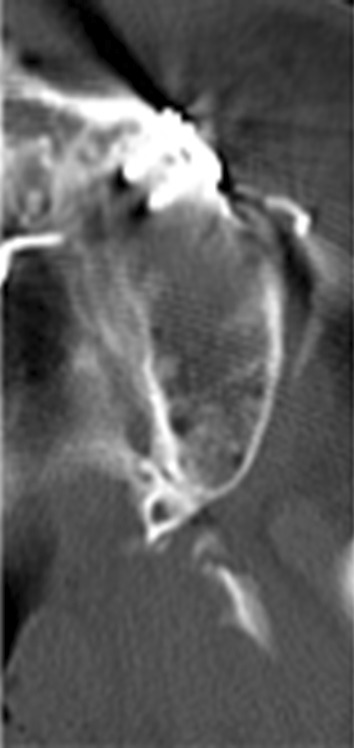

Four patients (Group I) underwent classic pterygomaxillary dysjunction technique in which separation occurs between posterior wall of the maxilla and the pterygoid plates as described by Bell for the classic technique group. The lateral wall of the maxilla was osteotomized with a 702 bur and the lateral nasal wall was osteotomized with a lateral nasal osteotome. The cartilaginous septum and vomer were separated with a nasal septum osteotome, and the curved pterygoid osteotome was used to separate the maxilla from the pterygoid plates. Preoperative and post-operative CT images of one of the patients operated by this technique has been shown for better understanding of the cut in the pterygomaxillary region (Fig. 1).

Fig. 1.

Preoperative and postoperative CT image of a patient operated by classic pterygomaxillary dysjunction technique. Arrow denotes the cut at the pterygomaxillary junction